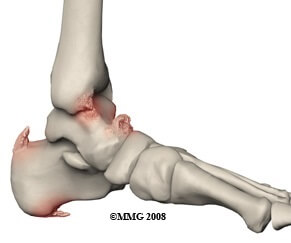

Small, outgrowths of bone that can irritate the surrounding structures

Causes: Friction on the bone from overuse, muscle tightness or tight footwear

Symptoms: Hard lump, localised pain, stiffness, secondary problems e.g. callus formation & nerve irritation

Full Article: Bone Spurs